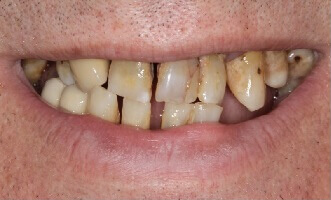

Probleem. Mitmekordsed karioossed kahjustused hammastel, suur hammaste väärarengute tase.

Lahendus. Halva hambaprognoosi tõttu eemaldati ülejäänud hambad ja paigaldati neli hambaimplantaati ülemisse ja alumisse lõualuusse. Implantaadid toetati metallist keraamiliste kroonidega.